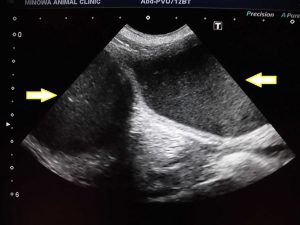

夜の子宮蓄膿症手術